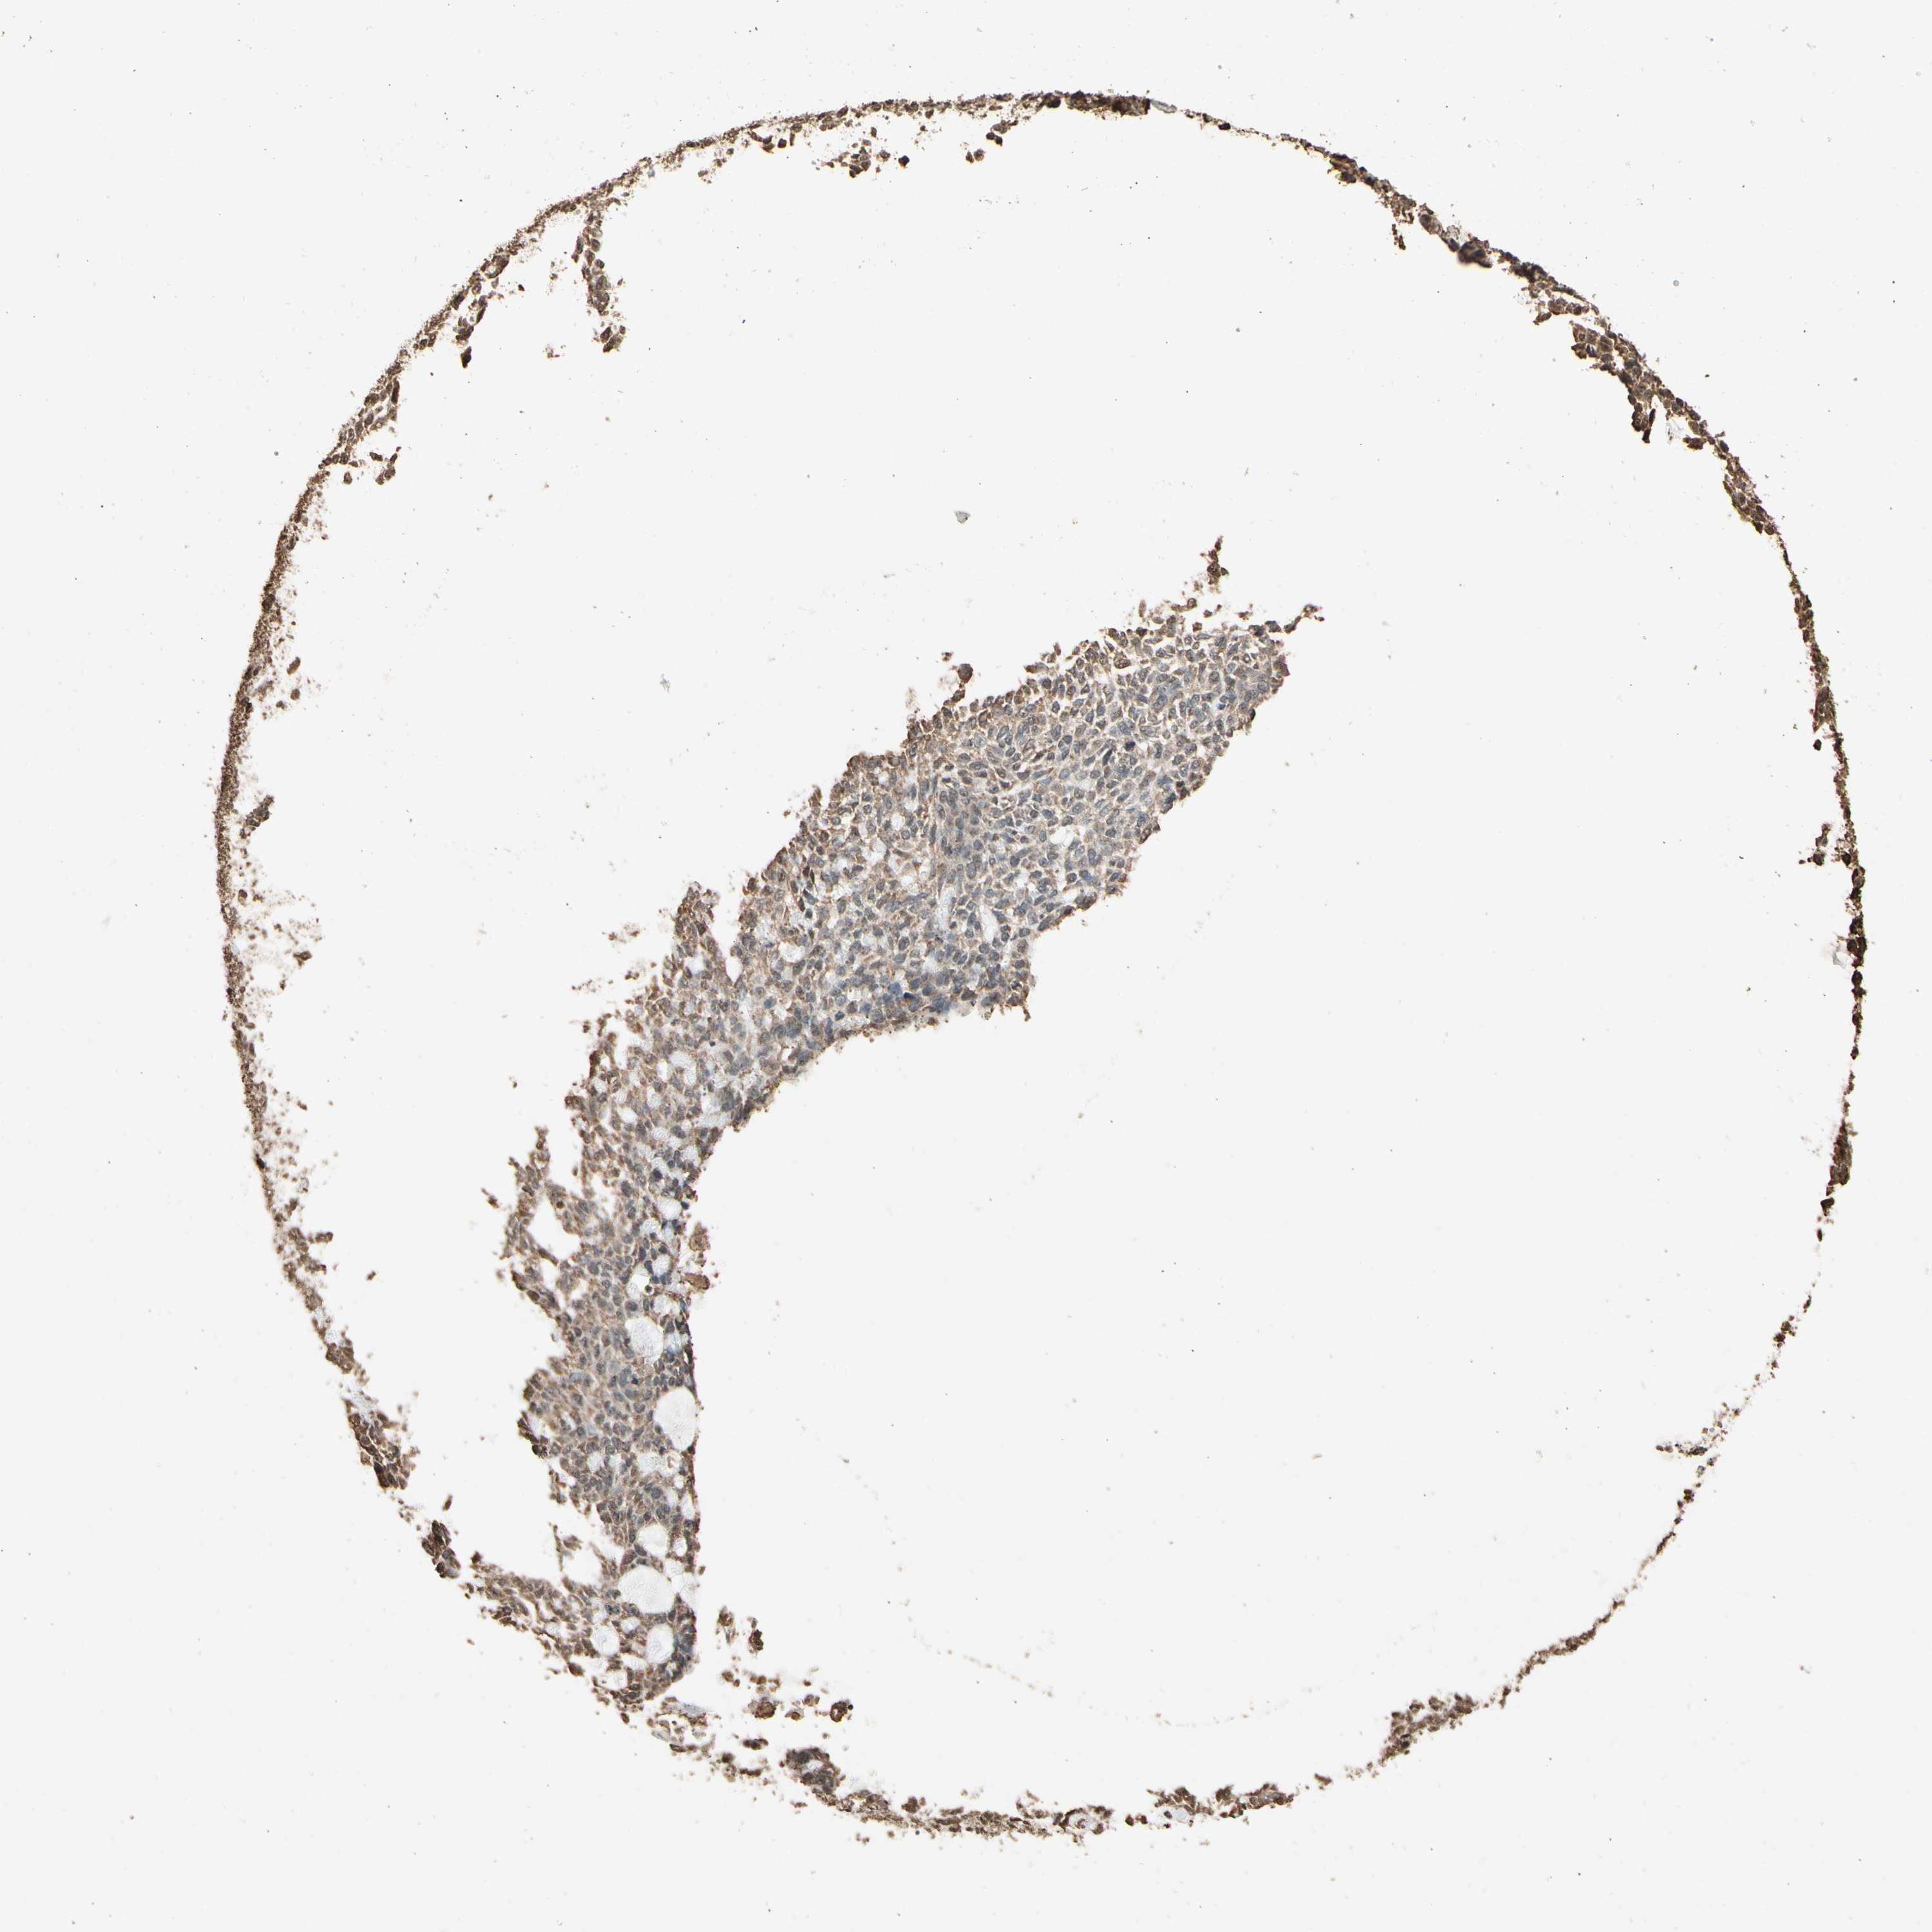

Basal cell and squamous cell cancer

SKIN CANCER - Protein expressioni

A mouse-over function shows sample information and annotation data. Click on an image to view it in a full screen mode. Samples can be filtered based on level of antibody staining by selecting one or several of the following categories: high, medium, low and not detected. The assay and annotation is described here.

Antibody stainingi

Antibody staining in the annotated cell types in the current human tissue is reported as not detected, low, medium, or high, based on conventional immunohistochemistry profiling in selected tissues. This score is based on the combination of the staining intensity and fraction of stained cells.

Each image is clickable and will lead to virtual microscopy that enables deeper exploration of all samples and also displays staining intensity scores, fraction scores and subcellular localization as well as patient and tissue information for each sample.

Antibody CAB009188

Staining

High

Medium

Low

Not detected

Intensity

Strong

Moderate

Weak

Negative

Quantity

>75%

75%-25%

<25%

None

Location

Nuclear

Cytoplasmic/membranous

Cytoplasmic/membranous,nuclear

Squamous cell carcinoma, NOS

Basal cell carcinoma